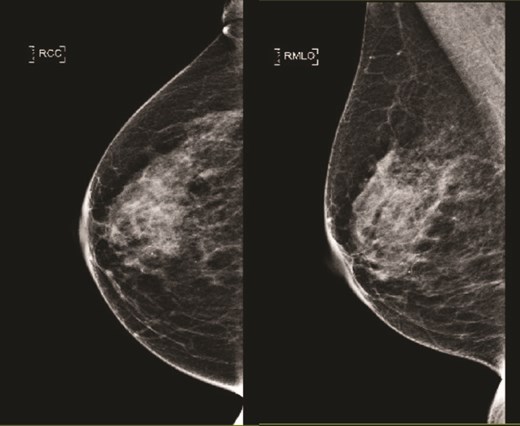

(Left) Mammography cranial-caudal view of right breast; (Right) Mammography mediolateral oblique view of the right breast: Both showing few loose clusters of faint and punctate microcalcifications in the upper outer right breast with no suspicious linear or tight cluster of microcalcifications.

(Left) Mammography cranial-caudal view of left breast; (Right) Mammography mediolateral oblique view of the left breast: Left upper outer breast spiculated mass with minimal architectural distortion.